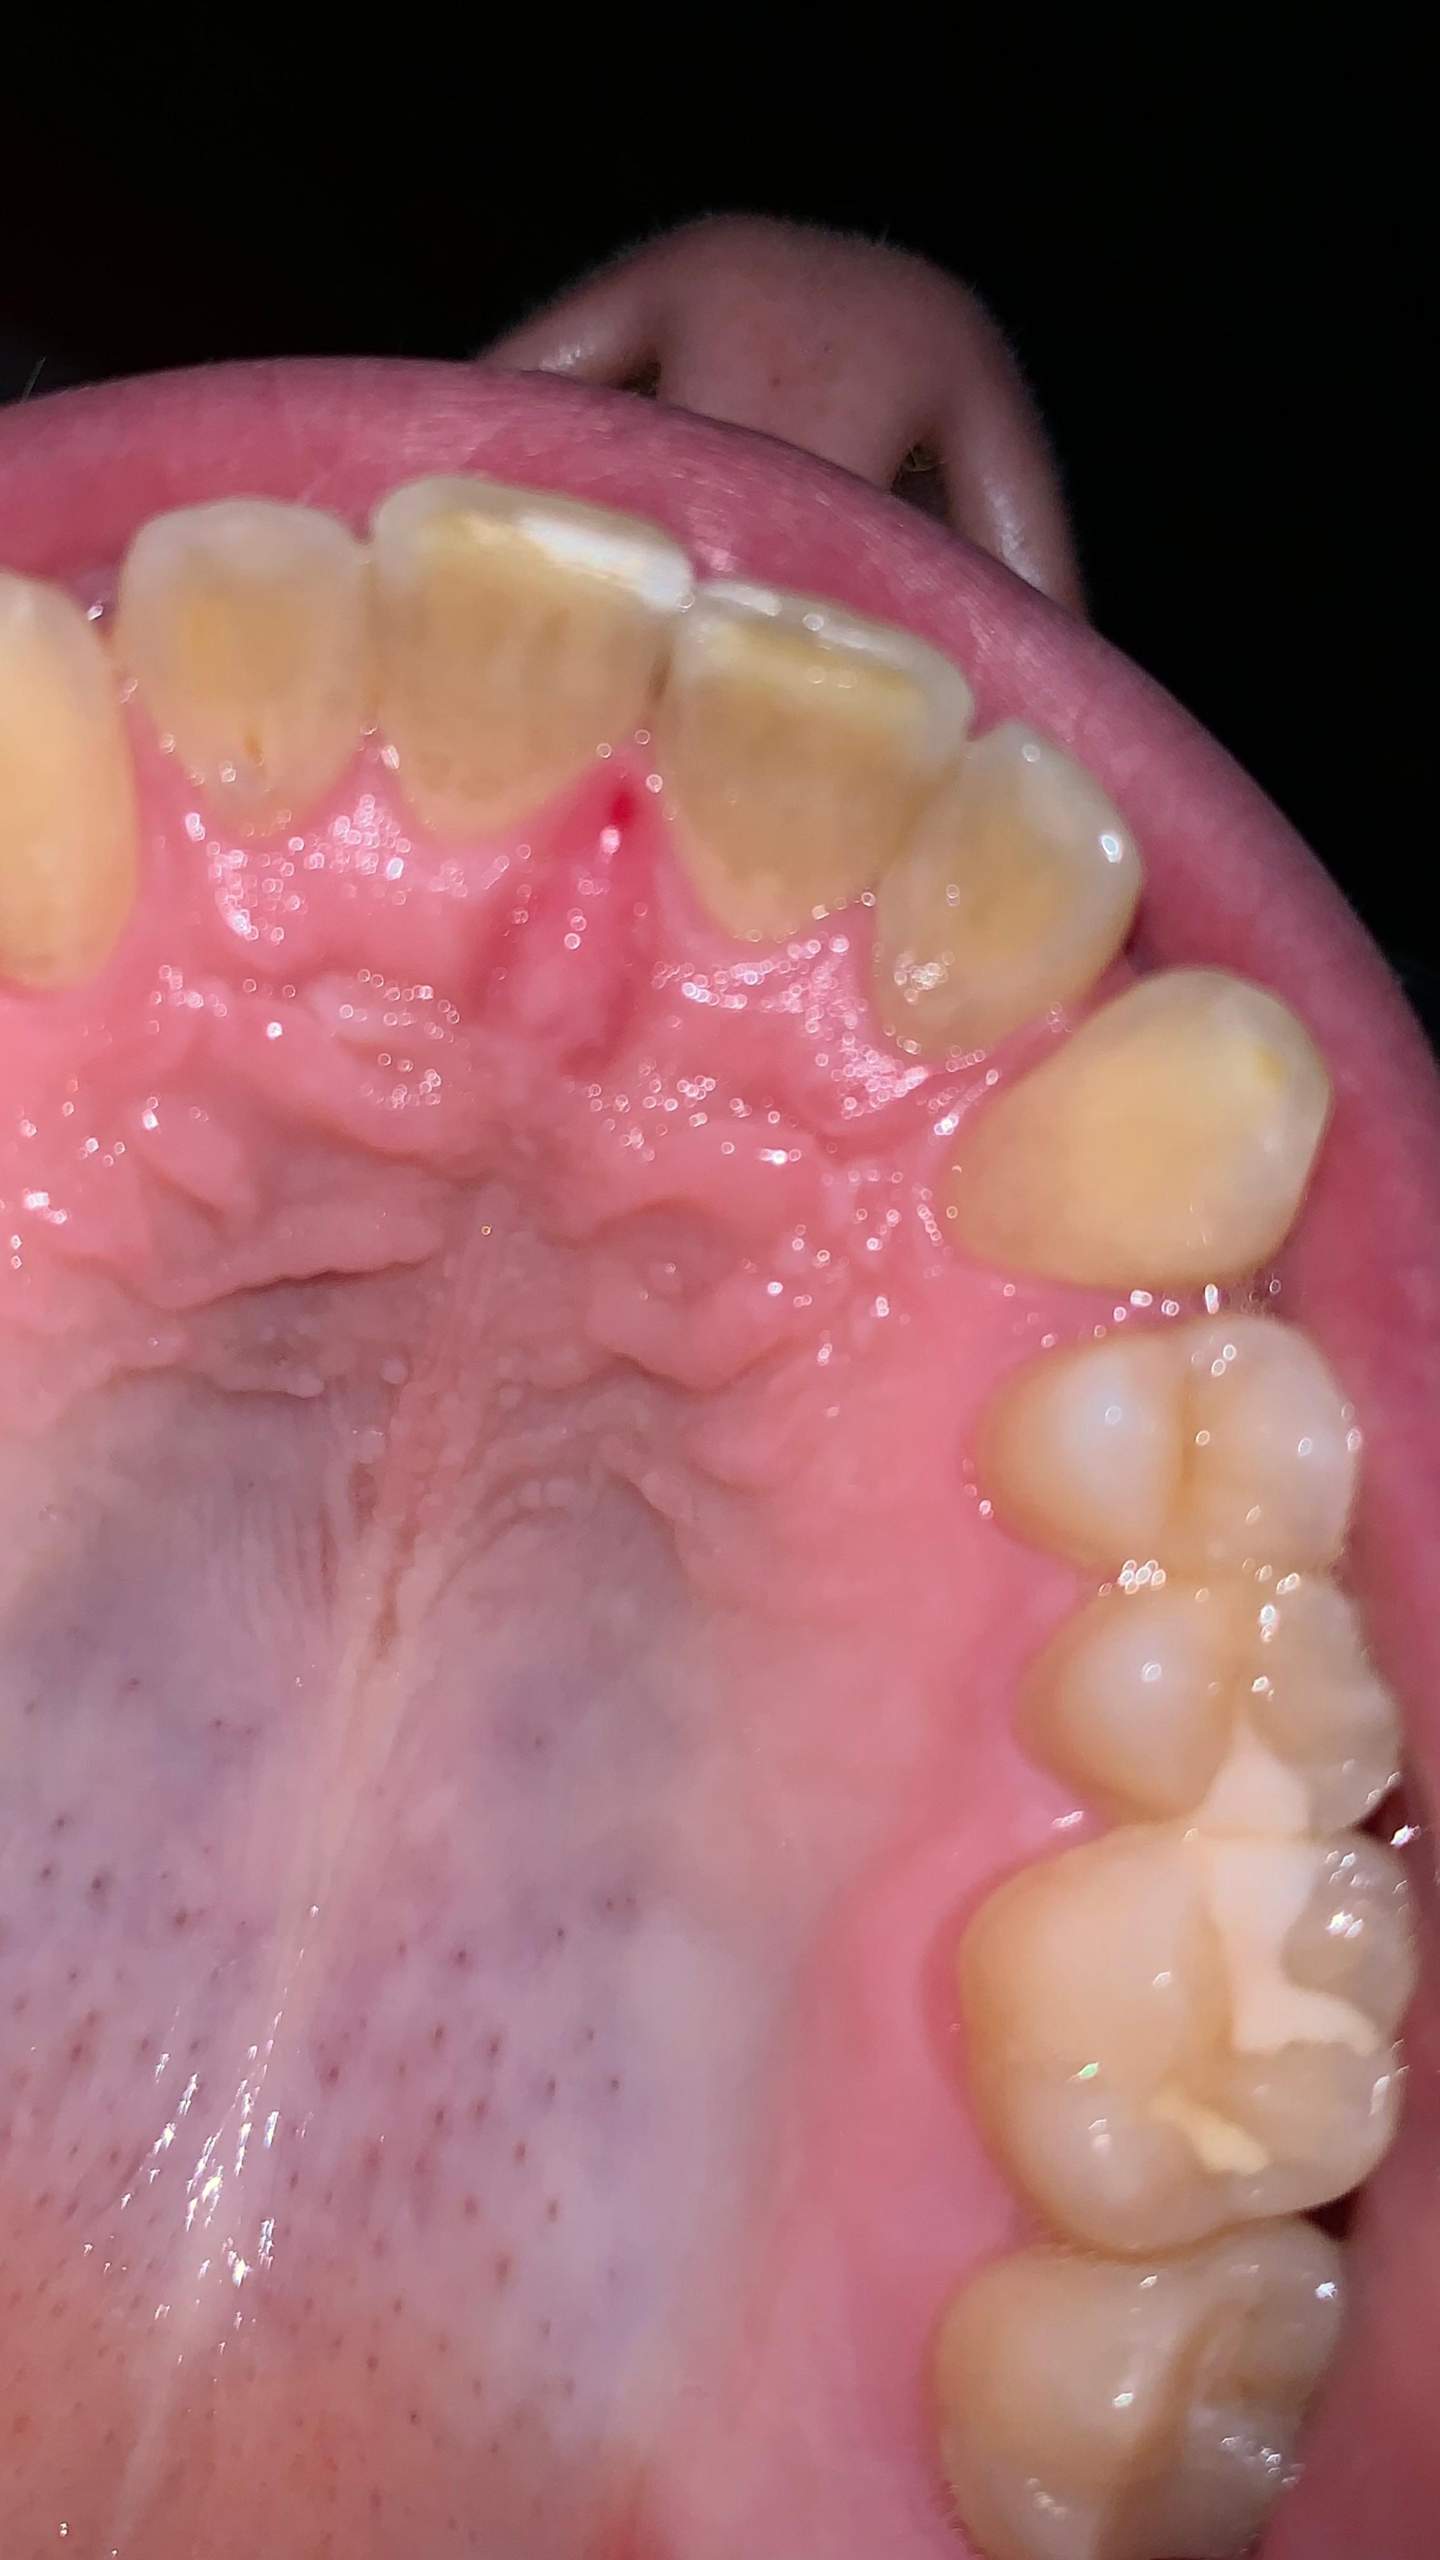

Eine Schwellung des Zahnfleisches ist ein Anzeichen für eine Entzündung. Hierbei wird Flüssigkeit im Gewebe eingelagert, welches durch eine Allergie oder Infektion hervorgerufen werden kann. Weitere Auslöser können sein: ein traumatischer Zahnunfall oder eine Verletzung. Ödeme. Blutungen. Fisteln am Zahnfleisch.. Auch eine Schwellung der betroffenen Areale (z. B. am Zahnfleisch, Gaumensegel, Gaumenzäpfchen, den Gaumenmandeln oder dem allgemeinen Oberkiefer) ist ein klassisches Entzündungszeichen. Begleitende Bläschen können auf einen Virenbefall oder Aphthen hindeuten. Gelbweiße Eiterherde weisen normalerweise auf eine Bakterienbesiedlung hin.

Geschwollenes Zahnfleisch ECDI

Zahnfleischentzündung Denta Beaute